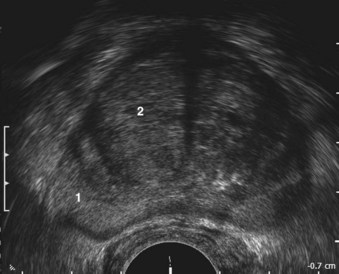

The glandular elements of the prostate have been divided into discrete zones, distinguished by the location of their ducts in the urethra, by their differing pathologic lesions, and, in some cases, by their embryologic origin (see Fig. 2–36). These zones can be demonstrated clearly with transrectal ultrasonography (Fig 2–39). At the angle dividing the preprostatic and prostatic urethra, the ducts of the transition zone arise and pass beneath the preprostatic sphincter to travel on its lateral and posterior sides. Normally, the transition zone accounts for 5% to 10% of the glandular tissue of the prostate. A discrete fibromuscular band of tissue separates the transition zone from the remaining glandular compartments and may be visualized at transrectal ultrasonography of the prostate. The transition zone commonly gives rise to benign prostatic hypertrophy, which expands to compress the fibromuscular band into a surgical capsule seen at enucleation of an adenoma. It is estimated that 20% of adenocarcinomas of the prostate originate in this zone.

Figure 2–39 Transrectal ultrasound of the prostate demonstrating the 1, peripheral zone and 2, transition zone.